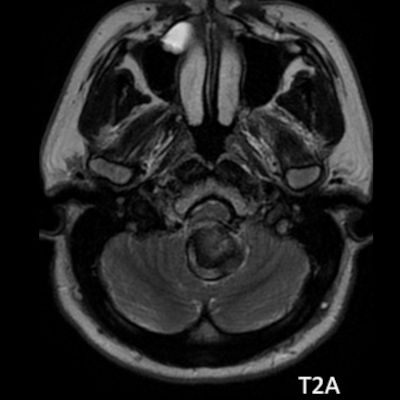

- A. Posterior fossada, T2A, T1A görüntü ve SWAN sekanslarda, 3.5 cm boyutta, düzgün sınırlı, T1A hiperintens, T2A hipointens heterojen iç yapıda kitlesel lezyon izleniyor (çember). Lezyonun serebellum ve kraniyoservikal bileşkeye bası etkisi mevcuttur (ok). Lezyon periferinde T1A, T2A ve SWAN görüntülerde hiperintens tubuler yapı bulunmaktadır (ok). Bu yapı intralezyonel “yılanvari eksantrik vasküler’’ yapıdır.

- MR

- Kısmen tromboze olmuş dev serebral anevrizma, kan ürünlerinin değişken yaşına bağlı olarak MRG’de heterojen bir sinyale sahiptir.

- T1 kısmen tromboze anevrizmada genellikle hiperintens odaklarla heterojen

- T2 kısmen tromboze anevrizmada genellikle hipointens odaklarla heterojen, serpantin anevrizma içi damar kanalında akım boşlukları, bitişik parankimde vazojenik ödem görülebilir.

- T2 ve SWAN genellikle santral-çevresel duyarlılık artefaktları görülür.